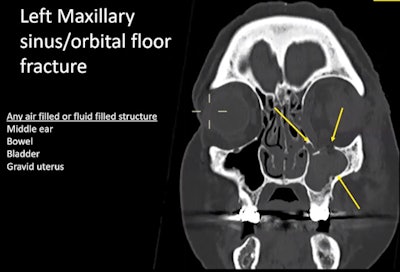

Radiologists should be aware of how injuries from different types of weapons may present on CT scans, according to Dr. Elizabeth Dick, consultant radiologist at London's Imperial College NHS Trust. She drew attention to the principles of blast physics, in which the primary high-pressure blast wave will affect air-filled and fluid-filled structures such as the sinuses and bladder.

Although fractures and bleeding to other structures such as the maxillary sinus can be seen very clearly on CT, she urged imagers to consider a facial x-ray initially and perform the CT scan later as high patient numbers and CT demand after a mass casualty incident may be overwhelming.